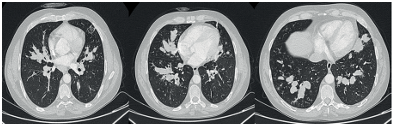

A forty-three-year-old male patient, under follow-up for asthma for the past two years, presented with increased shortness of breath, dark sputum, and hemoptysis for the last month. The patient had been diagnosed with nasal polyposis for four years and underwent nasal polypectomy surgery two years ago. He has a history of smoking four packs a year, and coarse rales were noted during the physical examination. Other systemic examinations were unremarkable. Due to the presence of a non-regressing consolidated area on the chest X-ray, a chest CT was performed (Figure 1). The chest CT revealed dilated bronchi filled with high-density mucus in a central distribution throughout all lobes of both lungs. The patient was admitted to our service with a preliminary diagnosis of allergic bronchopulmonary aspergillosis (ABPA). The admission white blood cell count was 19,000 with neutrophils at 53% and eosinophils at 31%. The total IgE was 1229, and the sed rate was 59. The patient’s skin prick test for Aspergillus was negative, as were Aspergillus-specific IgE and galactomannan tests. Bronchoscopy was performed, revealing widespread dark secretions in both lungs. The cytology of bronchoalveolar lavage was eosinophil-rich. Radiologically and clinically, the patient was diagnosed with ABPA, and treatment with prednisolone and itraconazole was initiated.

Figure 1. Dilated bronchi filled with high-density mucus in a central distribution throughout all lobes of both lungs.